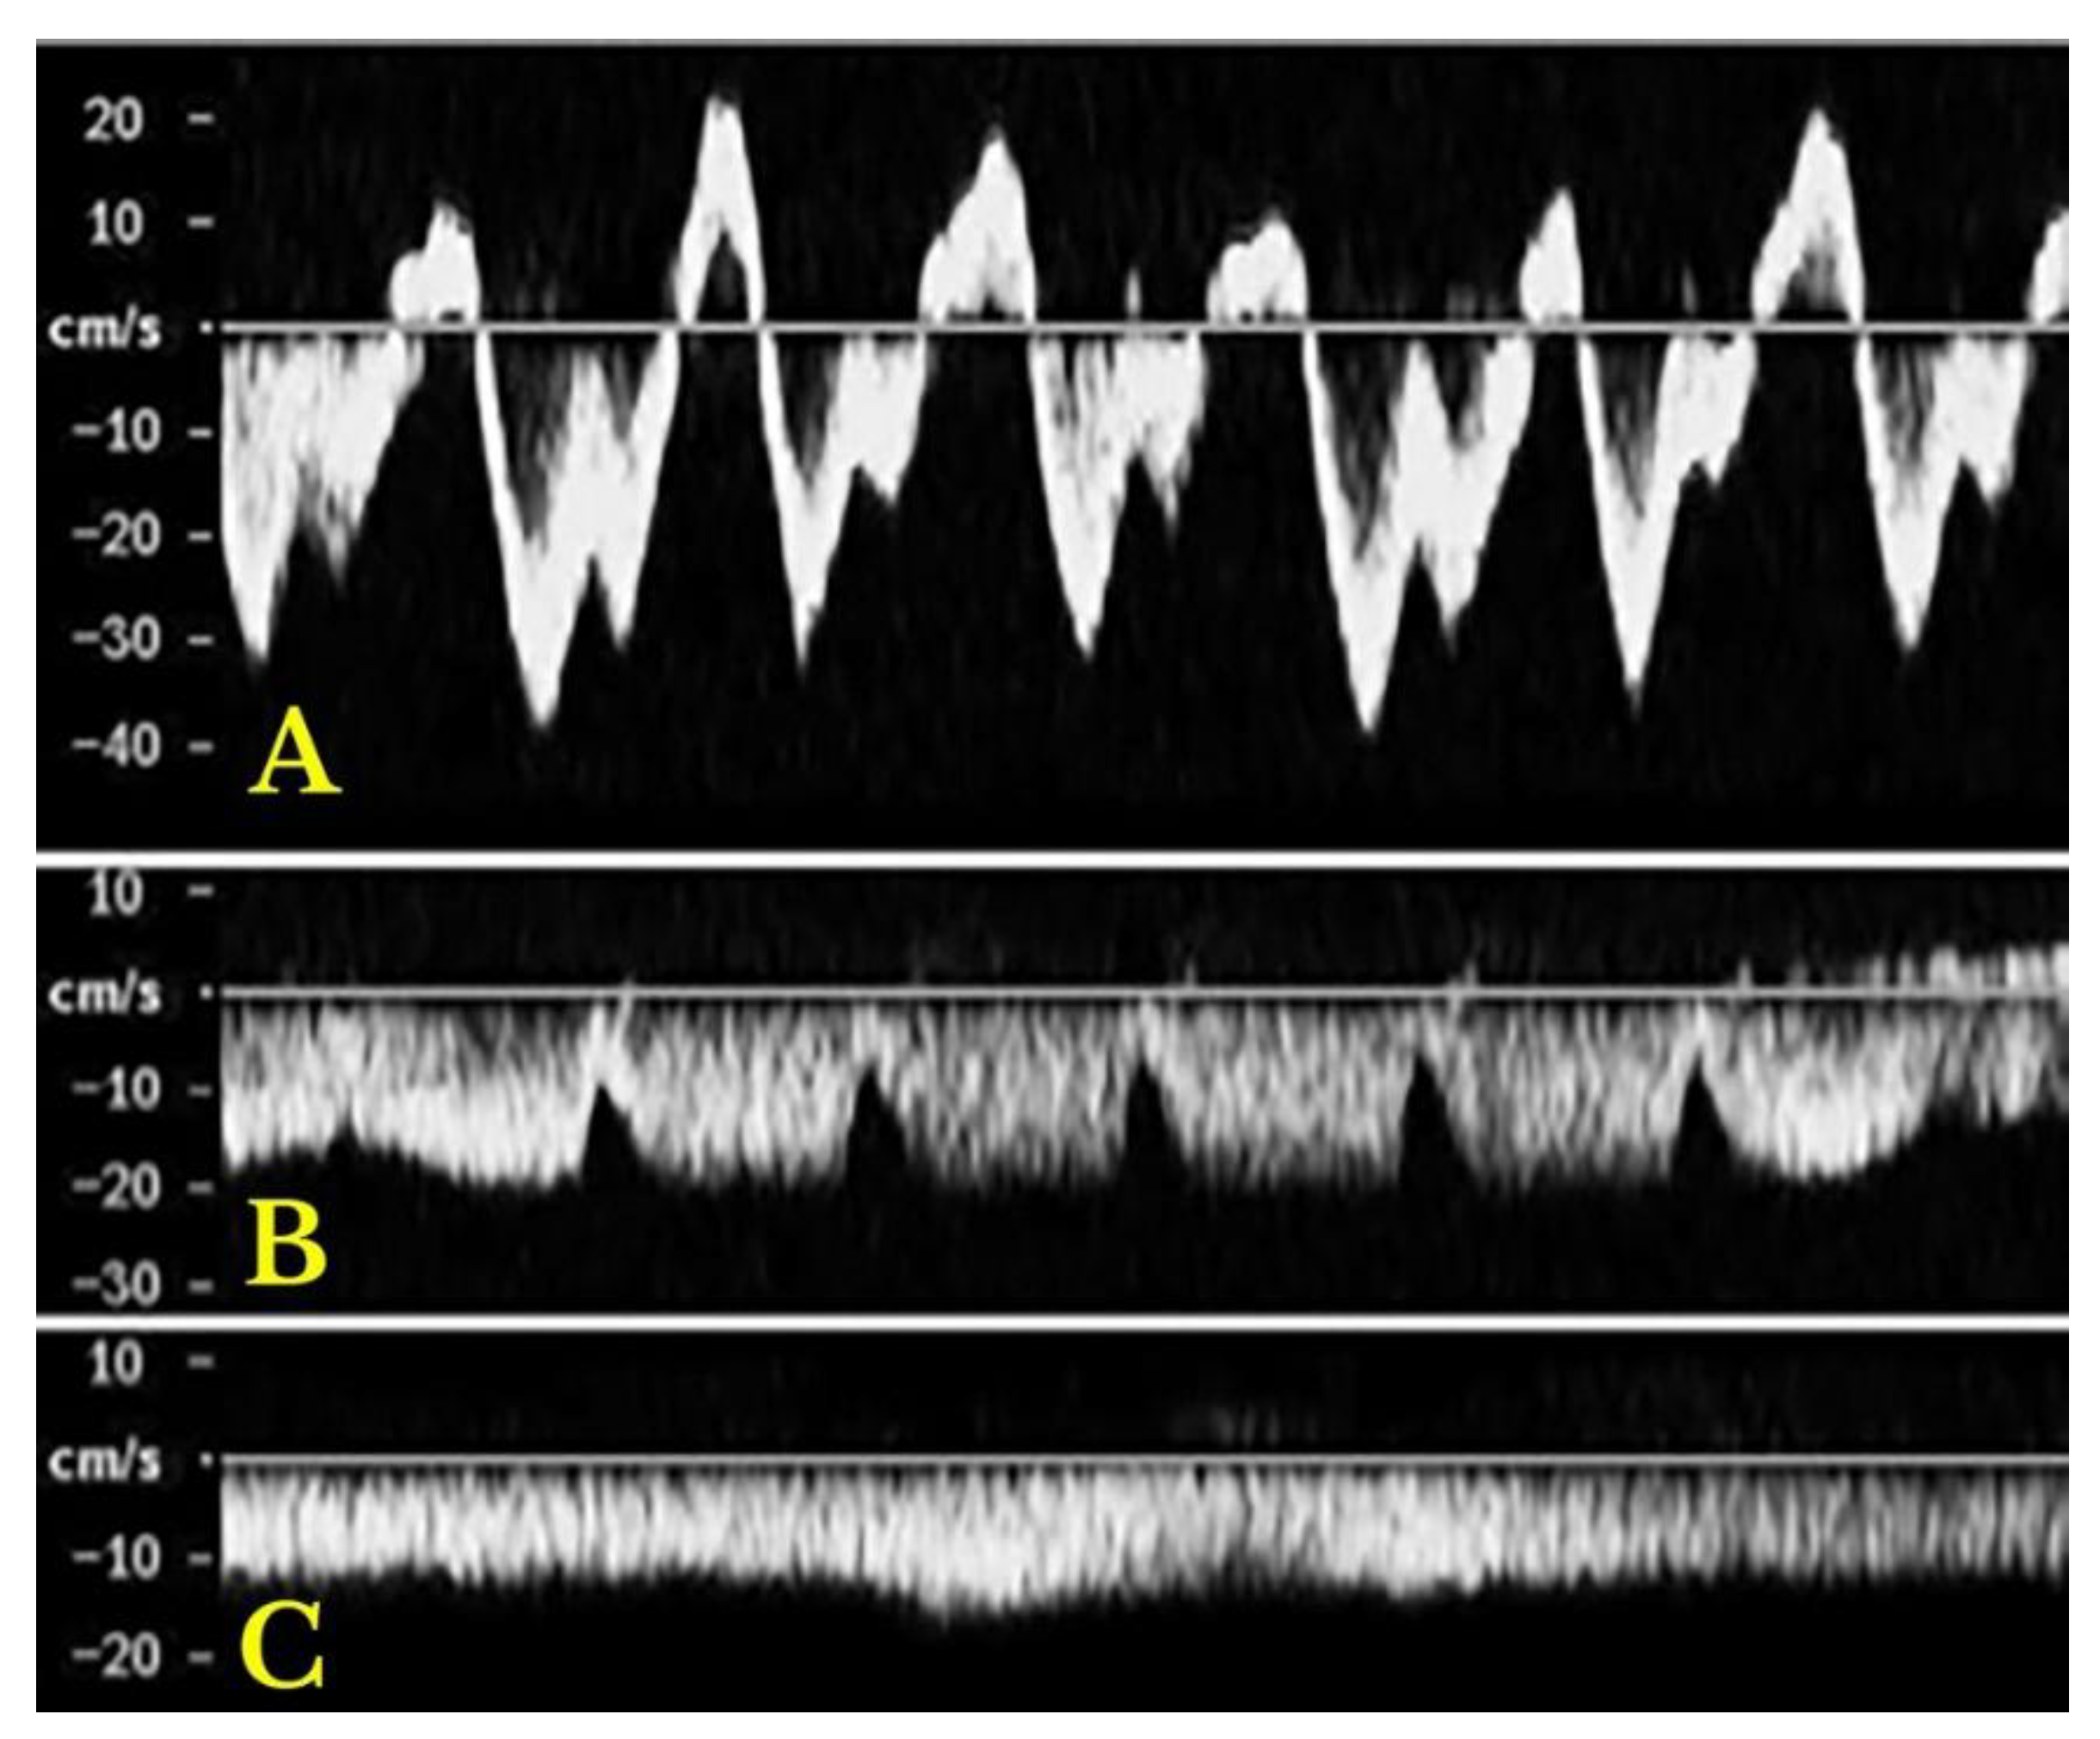

HEPATIC VEINS:

| Intrahepatic veins | Portal vein | Hepatic artery | |

|---|---|---|---|

|

Normal |

Triphasic pattern: "a" wave: positive, "a" > "v" "S" wave: negative, "S" > "D" "v" wave: positive; "v" < "a" "D" wave: negative, "D" < "S" |

Anterograde flow Smoothly undulating venous waveforms Systolic speed 16–40 cm/s Pulsatility index > 0.5 |

Maximum systolic speed: 30–60 cm/s Resistive index 0.55–0.7 |

Heart failure |

Increased anterograde and retrograde speeds | All cases of hepatic congestion | |

| Increased pulsatility | |||

| Right heart | Higher “a” and “v” waves | ||

| failure | Adequate ratio maintained between S and D waves |

Pulsatility index < 0.5 |

Resistive index > 0.7 |

| High and both positive “a" and "v" waves |

Reduced systolic speed | ||

| Tricuspid regurgitation | Reduced “S” wave “S” wave < “D” wave |

(more common in LC) |

| *Severe TR: "S" wave retrograde (“a-S-v complex”) | |||

| Liver cirrhosis |

Loss of triphasic pattern |

Systolic speed <12.8 cm/s till reversal flow and thrombosis |

- Altinkaya, N.; Koc, Z.; Ulusan, S.; Demir, S.; Gurel, K. Effects of respiratory manoeuvres on hepatic vein Doppler waveform and flow velocities in a healthy population. Eur J Radiol 2011, 79, 60-63. [CrossRef]

- Kim, M.Y.; Baik, S.K.; Park, D.H.; Lim, D.W.; Kim, J.W.; Kim, H.S.; Kwon, S.O.; Kim, Y.J.; Chang, S.J.; Lee, S.S. Damping index of Doppler hepatic vein waveform to assess the severity of portal hypertension and response to propranolol in liver cirrhosis: a prospective nonrandomized study. Liver Int 2007, 27, 1103-1110. [CrossRef]